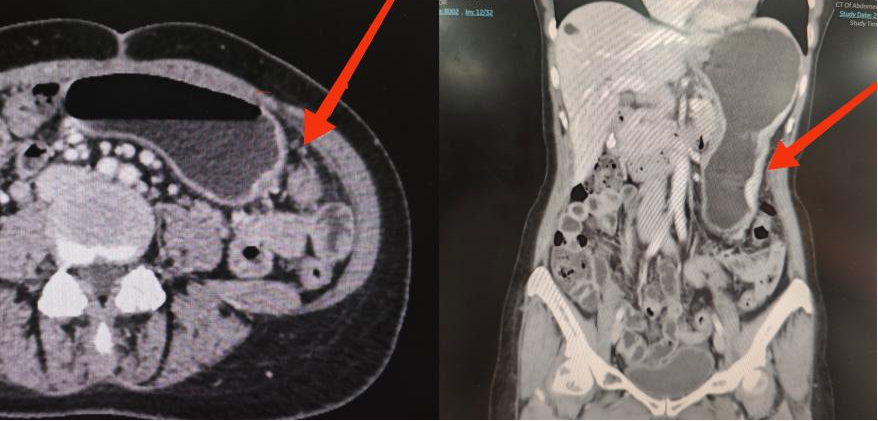

Aria术前影像报告,箭头处为转移病灶

来到清华大学附属北京清华长庚医院腹膜肿瘤科主任李雁的门诊时,Aria在新西兰已经经历过2次手术、4周期新辅助化疗,但依然未能阻挡胃癌腹膜转移对她健康的摧残。对生的渴望已经突破了国家的界限,Aria(化名)和家属将目光放到国外的专家上。在经历了数次搜索后,他们在网络上看到了李雁主任。家人通过大使馆与李雁主任进行多次沟通与协调后,最终决定来到北京清华长庚医院寻求机会。

可能是因为语言的障碍,也有可能是因为多次治疗后的无助,初次来到门诊的Aria看起来并没有什么信心。而李雁在诊疗过程中,以自己和团队的专业水平,逐步给了他们生的希望,顺畅的英语交流更是扫除了交流的最后一丝障碍。在术前进行MDT评估后,李雁团队制定了完善的手术方案:先通过细胞减灭术切除肉眼可见的肿瘤,再通过腹腔热灌注化疗消灭残余肿瘤组织和游离肿瘤细胞,力求彻底消灭腹腔内原发肿瘤和转移灶。